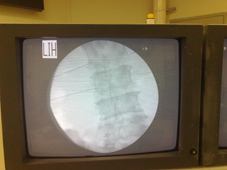

圖、以X光機透視下將探針精準插入腰椎的小面關節,準備開始治療。

圖、高頻熱凝療法治療下背痛

超過百分之九十的下背痛其實和所謂骨刺、椎間盤突出、神經壓迫等等沒有關係,反而多半是肌肉發炎、關節發炎居多,高頻熱凝療法在這方面的治療成效相當卓越,尤其對於所謂腰椎小面關節炎所造成的下背痛,有超過八成的治癒率。